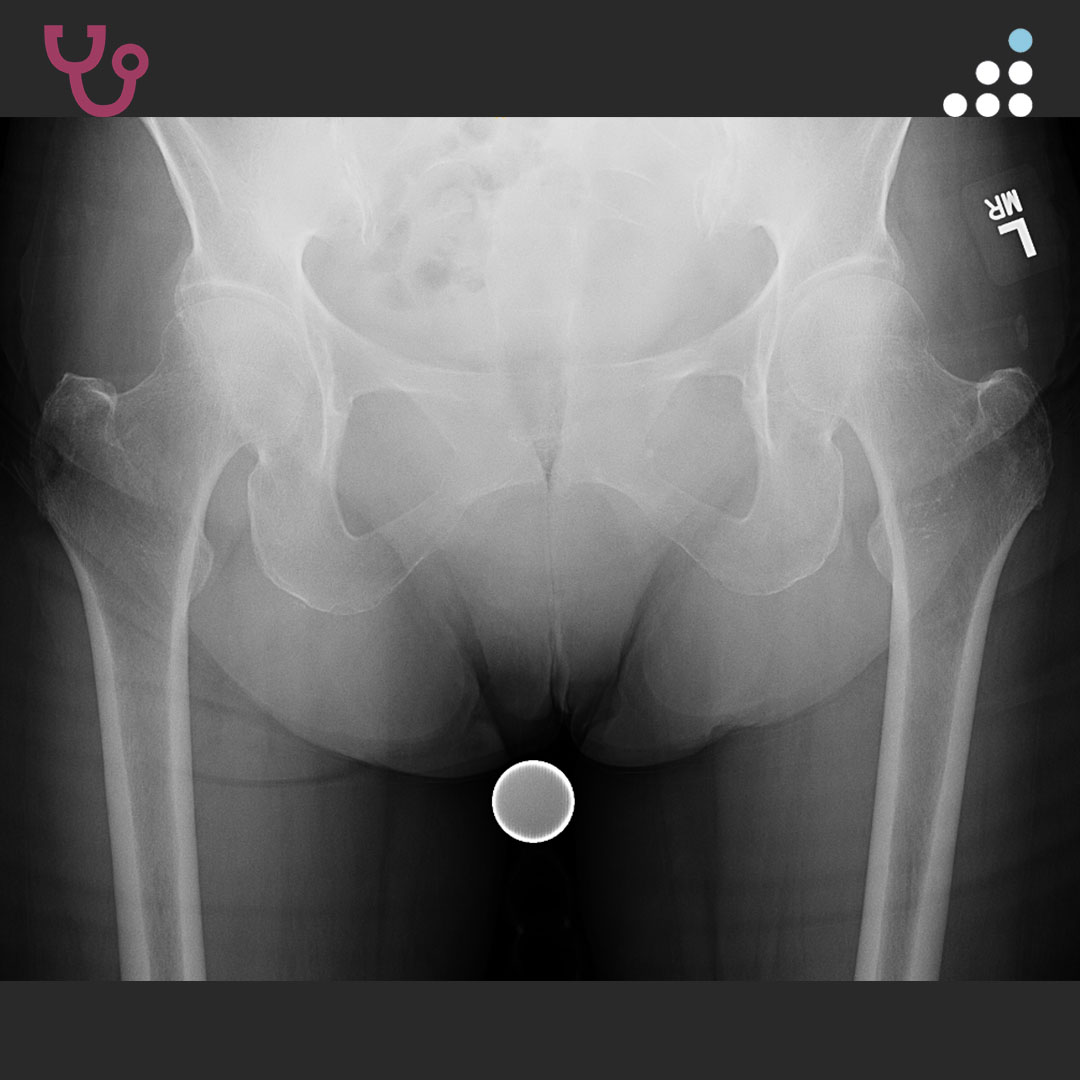

DYSPLASTIC HIP IN 20M WITH CEREBRAL PALSY